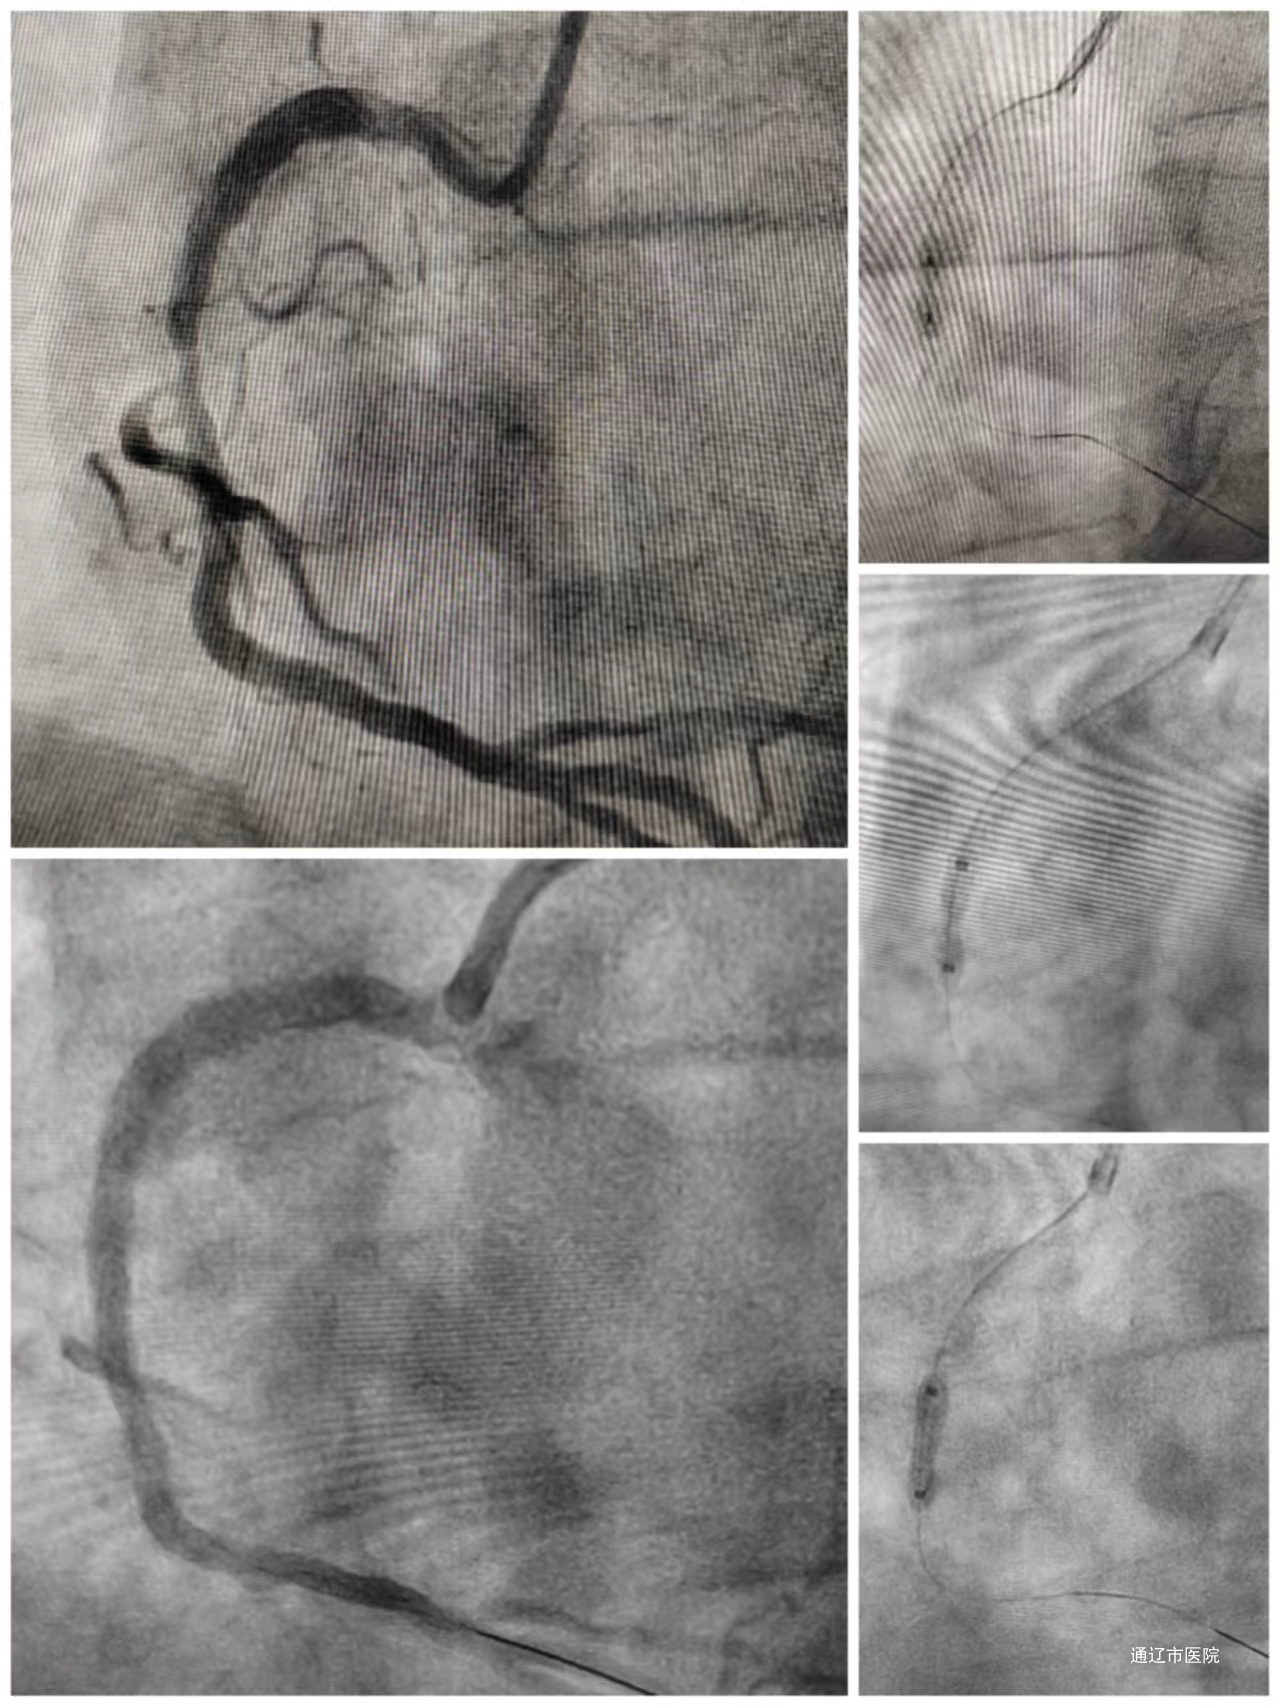

1月29日,我院心血管内三科负责人郑崔成带领介入团队,成功应用“Shockwave冲击波球囊技术”,完成我院首例严重狭窄冠心病变介入治疗手术。

一名66岁男性患者,半个月前因频繁胸痛而被送入我院治疗。冠脉造影检查结果显示右冠状动脉支架内存在高达85%的严重狭窄,实施高压球囊导管扩张效果不佳。考虑到患者病情的特殊情况,心内三科的介入团队再次对病变进行全面评估,最终决定采用国际领先的技术——“Shockwave冲击波球囊”。术中进行了总计80次冲击波冲击,手术过程顺利,最终成功扩张了狭窄的冠状动脉病变。紧接着,通过对原支架应用药物球囊,实现无金属残留,患者术后的症状得到了显著改善,不再出现胸痛症状。

这项治疗采用的是经皮冠状动脉腔内冲击波球囊导管成形术,又称血管内碎石术(intravascular lithotripsy,IVL)。IVL在处理高度钙化的病变时表现出优越的修饰效果,同时显著减少了手术时间,为手术风险提供了更低的概率。值得一提的是,该技术于2018年在欧洲获批上市,在2021年获得美国食品药品监督管理局批准上市,而在2022年5月,已在中国获得批准,用于治疗冠状动脉钙化病变。